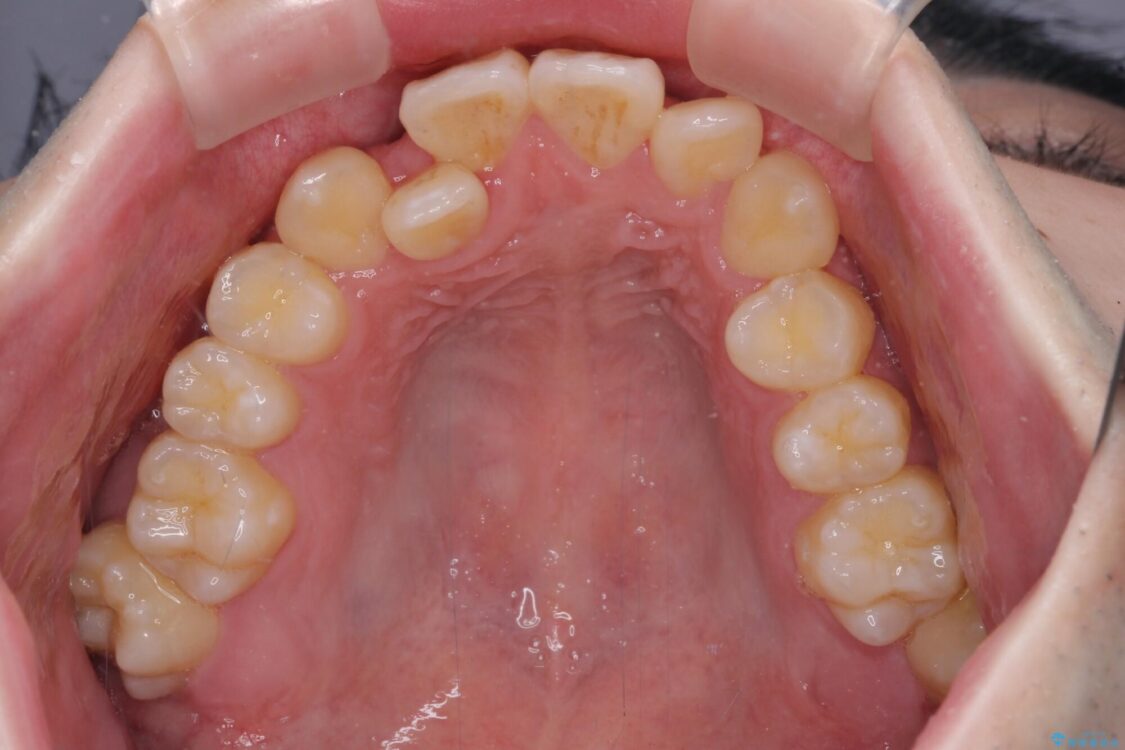

治療前

• 全顎的なクロスバイト 補助装置を用いてワイヤー矯正 治療前画像